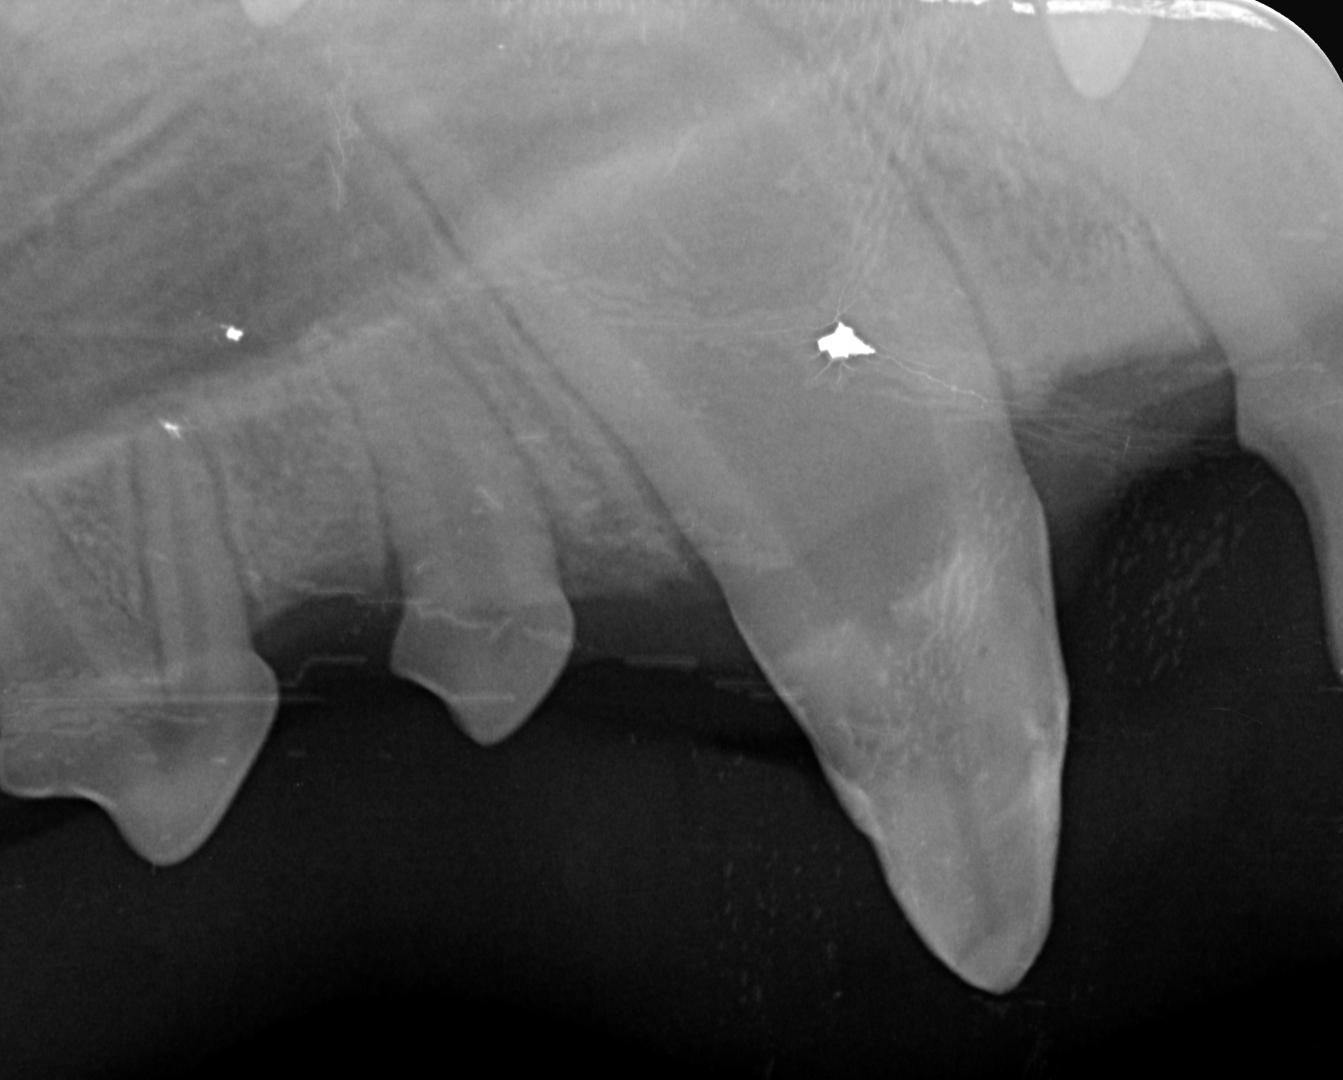

La radiographie est indispensable dans ce cas pour vérifier la meilleure conduite à tenir :

radio croc

Dans le cas d'Alphonse :

- l'apex est fermé (cercle vert) sur les 3 dents concernées ; aucun abcès n'est visible et donc la pulpe ne présente pas de signe de contamination (vérifié également par sondage, le canal n'est pas perméable)

- La couche de dentine semble déjà conséquente et suffisante pour donner une chance à la dent (trait bleu) ;

La décision est donc prise de tenter de la conserver, et de protéger la pulpe en déposant une couche de résine pour combler les surfaces abîmées du croc.